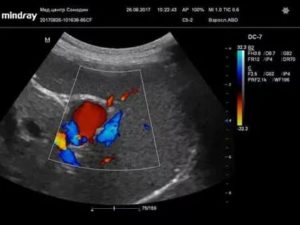

- УЗИ. Выявляют округлое анэхогенное (темное) образование в проекции селезенки или поджелудочной железы, заполненное кровью;

- Дуплексное сканирование. Метод используют для определения диаметра аневризмы и характера кровотока в ней;